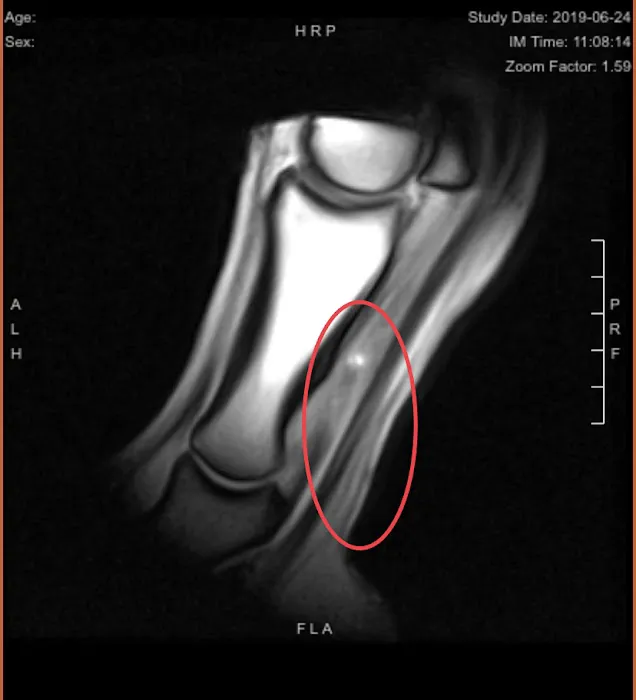

Equine MRI of MD, LLC Photos